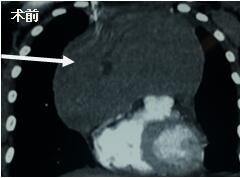

當(dāng)看到病人的CT等外院各項(xiàng)檢查時(shí),我頭皮發(fā)麻,心頭發(fā)怵:巨大的腫塊占據(jù)著整個(gè)縱隔,壓迫心臟,與血管關(guān)系密切,初步考慮侵襲性胸腺瘤、胸腺癌或淋巴瘤等,合并腎功能不全,無(wú)法完整切除,手術(shù)風(fēng)險(xiǎn)大,手術(shù)并不能提高病人長(zhǎng)期生存率,換言之,小伙子等待的是生命的立即終結(jié)。